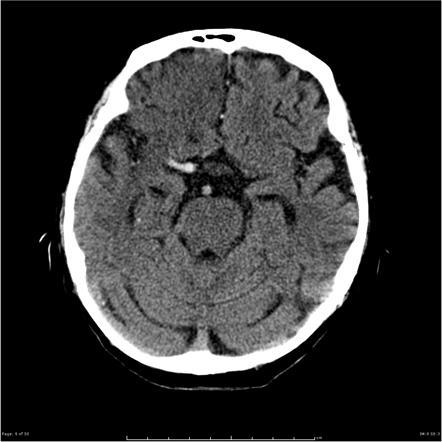

What does this CT show?

A

MCA ‘hyperdense artery’ sign

Indicates infarction